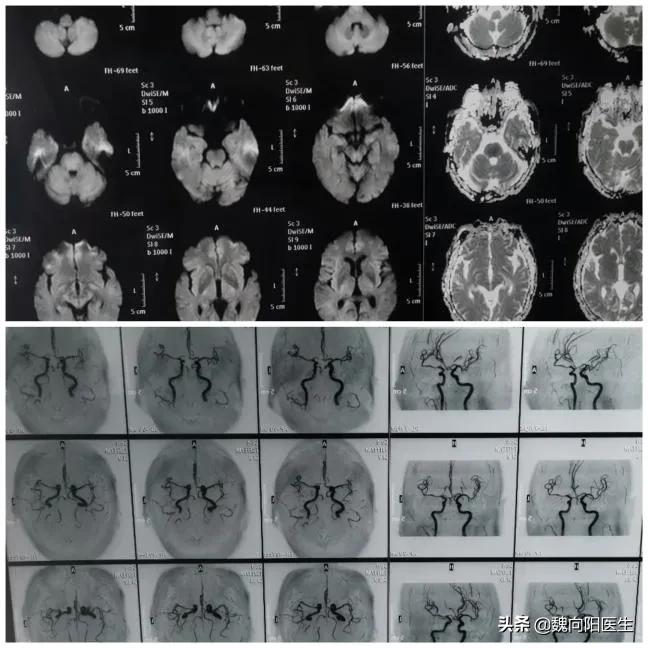

患者冯某,63岁,在早晨8:00左右突然出现意识不清楚,不能言语,不能自主活动,老伴急忙呼叫120后送至我院急诊就诊。急诊查体发现患者处于浅昏迷状态,刺痛患者无明显反应,不能配合查体。立即行头核磁发现是“脑干梗死,伴有基底动脉不显影”,诊断:脑梗死,基底动脉闭塞。医生告知患者老伴儿:患者目前病情危重,需要立即住院静脉溶栓治疗。患者既往体健,无过敏史,有一个女儿,常年生活在美国。当时老伴就处于懵的状态,只是知道点头,但却没有行动。在医生的指引下下才来到了病房。

患者转入病房后,医护已经做好溶栓前准备,在最快的时间内给予患者输入溶栓药物rt-PA(0.9mg/KG)。考虑患者脑梗死是由于大动脉闭塞导致的,医生建议患者立即行脑血管造影检查,但是患者老伴儿好像并没有认识到问题的严重性,只说需要打电话考虑一下,然后就在那默默的呆着。时间一点一点过去了,大约1小时后,医生只能再次反复的跟患者的老伴沟通:现在患者没有时间再等了,随着缺血的时间延长,越来越多的脑细胞在因缺血坏死,因此需要患者家属马上做决定。经过医生反反复复的催促患者老伴,才最终给患者姐姐打了一通电话,同意手术治疗。12:00终于把患者推进了导管室,在做脑血管造影过程中患者躁动明显,处于严重不配合状态,只能立即联系麻醉师,给予全麻。患者安静下来后立即做脑血管造影发现左侧椎动脉闭塞,右侧椎动脉是一个次全闭塞状态,狭窄的只剩下一根头发丝粗细的血管腔,颅内血供出院严重不足状态。给予植入一根血管支架后,立即恢复颅内的血供。手术做的很顺利,为了配合治疗,防止患者醒后再次躁动,保持患者镇静状态返回病房。